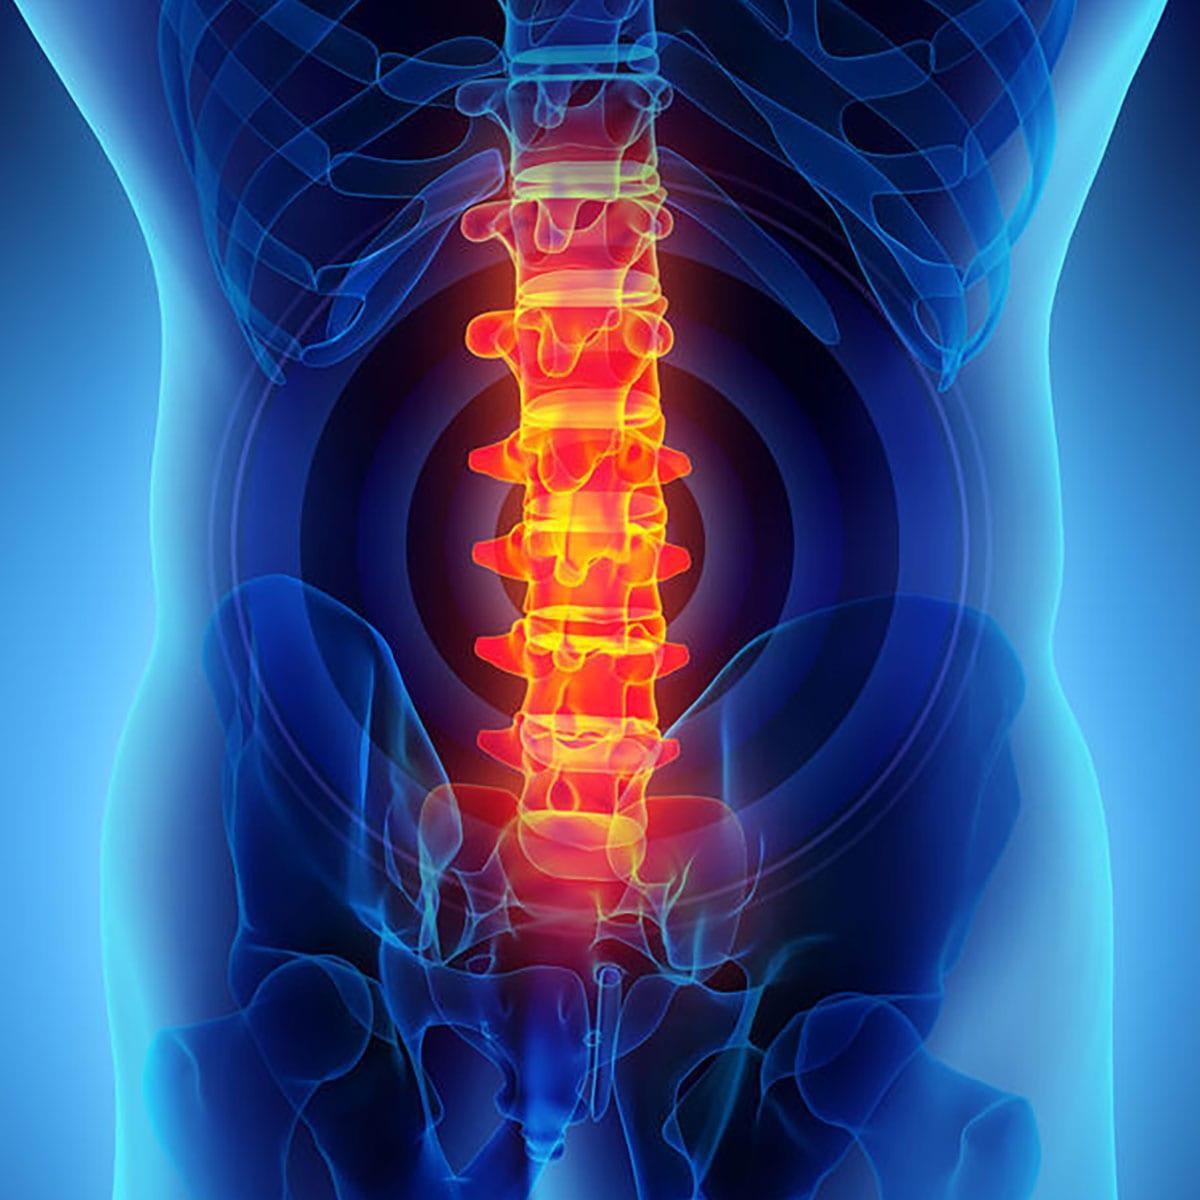

兩類腰骨痛

腰骨痛可以分為兩大類,一是由神經問題引起,另一個是肌肉或關節相關的。神經問題大多興椎間盤問題,或者神經根從脊椎走了出來,出現擠壓而疼痛。這些腰骨痛就需要找醫生診斷而作出適切治療。

然而脊椎兩旁的肌肉本來屬核心肌群的一部分,用於穩定脊椎,只提供小範圍的旋轉和屈曲,並不能補足臀部肌力太弱的問題,因此久而久之就會過度繃緊、疼痛。所以只要解決臀部太弱的問題,就可解決腰骨痛。